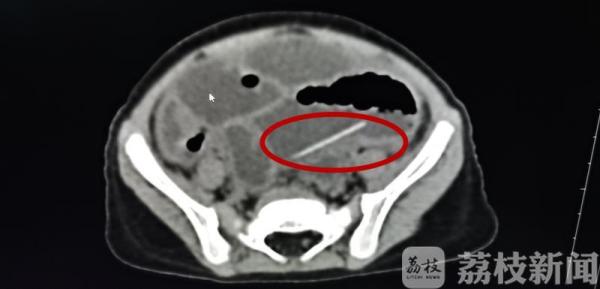

前两天,菲菲(化名)出现反复呕吐症状,家人急忙带她到医院就诊。医生询问病史时,家长表示孩子没有吃什么不洁食物,也没有受凉,呕吐来得很突然。“刚开始,孩子入住了儿科病房,但症状越来越重,发烧、腹胀。经拍片发现,膈下有游离气体,表示腹腔有穿孔。我们又给孩子查个CT,发现盆腔里有一根大概3厘米长的非金属物品。”淮安市妇幼保健院小儿外科主任医师王寿青说。

医生立刻为菲菲安排了手术。“腹腔镜探查发现,‘罪魁祸首’是一根牙签,大概3厘米,肠壁穿了两个孔。”王寿青说,还好发现及时,否则后果不堪设想,“牙签一端是很锐利的,时间长了可能不是穿两个洞,有可能穿孔的地方很多,粪便通过穿孔进入腹腔会造成感染,孩子可能有生命危险。”